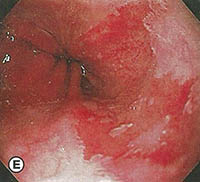

Όμως στον οισοφάγο Barrett, ο άπω οισοφάγος επενδύεται με κυλινδρικό επιθήλιο, που επεκτείνεται προς τα πάνω για μία μεταβλητή απόσταση, συχνά από 3cm μέχρι 10cm αλλά και περιστασιακά εμπλέκει το μεγαλύτερο τμήμα του οισοφάγου. Το εγγύς όριο του οισοφάγου μπορεί να είναι οριζόντιο ή μπορεί να υπάρξουν ανώμαλες, συχνά σχήματος γλώσσας επεκτάσεις του κυλινδρικού επιθηλίου. Πολλοί ασθενείς έχουν νησίδια αναγεννητικού ή υπολειμματικού πλακώδους επιθηλίου, ενώ άλλοι παρουσιάζουν διάσπαρτα καλοήθη έλκη στην κυλινδρική περιοχή. Οισοφαγικές στενώσεις και οισοφαγίτιδα ίσως, να διαφαίνονται επί της ΝΕΑΣ συμβολής (πλακώδους – κυλινδρικού επιθηλίου). Επίσης, κατά την ενδοσκόπηση θα πρέπει να αναζητείται ένδειξη για αδενοκαρκίνωμα, όπως αυτή των οζιδίων ή μαζών.

Το χαρακτηριστικό ιστολογικό εύρημα στον οισοφάγο Barrett είναι το διακριτό, εξειδικευμένο εντερικό επιθήλιο. Αυτό καταλαμβάνει το μεγαλύτερο μέρος ή και όλη την περιοχή που καλύπτεται απο κυλινδρικό επιθήλιο και είναι ο τύπος του επιθηλίου όπου το αδενοκαρκίνωμα αναδύεται. Άλλοι τύποι επιθηλίων που διαφαίνονται με οισοφάγο Barrett είναι τα επιθήλια τύπου γαστρικού θόλου και καρδίας, αλλά αυτά από μόνα τους δεν φτιάχνουν τη διάγνωση του οισοφάγου Barrett, ούτε συσχετίζονται με αδενοκαρκίνωμα.